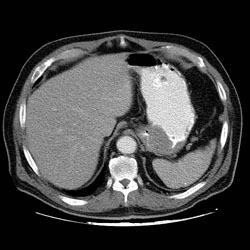

RADIOLOGY: GASTROINTESTINAL: GI: Case# 33697: LOCAL RECURRENCE VS. LOCAL REGIONAL METASTASES. CHOLELITHIASIS. 72 year old male with gastric lymphoma resected February 1997. Patient has weight loss and abdominal pain. 1. Hypodense mass adjacent to prior surgical site is most consistent with local recurrence vs. local regional metastases. No distant metastases are identified. 2. Cholelithiasis without evidence of cholecystitis. 3. Bilateral renal cysts and penile prosthesis reservoir unchanged.